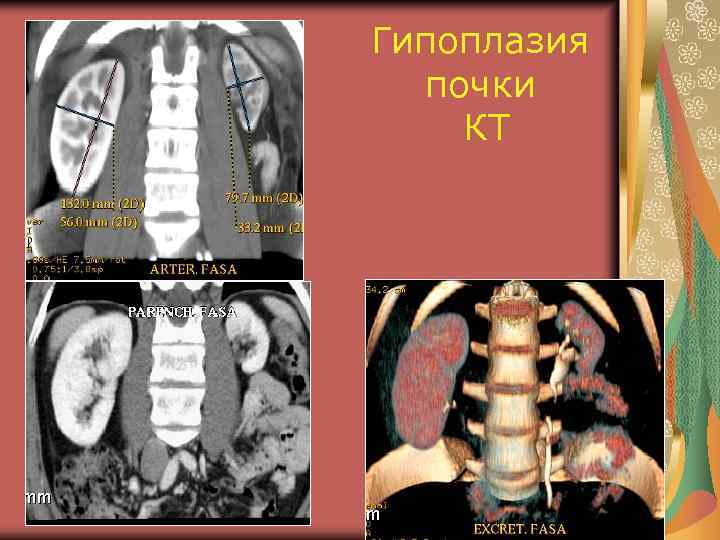

Аномалии величины Гипоплазия почки (0, 2%) Нормально сформированный орган маленьких размеров Причина – аномалия сосудов, аномалия закладки метанефроса Функция не нарушена Дифференциальный диагноз с первично и вторично сморщенной почкой

УЗ признаки гипоплазии Все размеры почки равномерно уменьшены. Объем меньше нормальной почки на 30% Структура почки обычная Контуры четкие, капсула прослеживается Дифференциация между паренхимой и срединным эхокомплексом и кортикомедуллярная дифференциация сохранены

КТ гипоплазия левой почки

Гипоплазия почки КТ